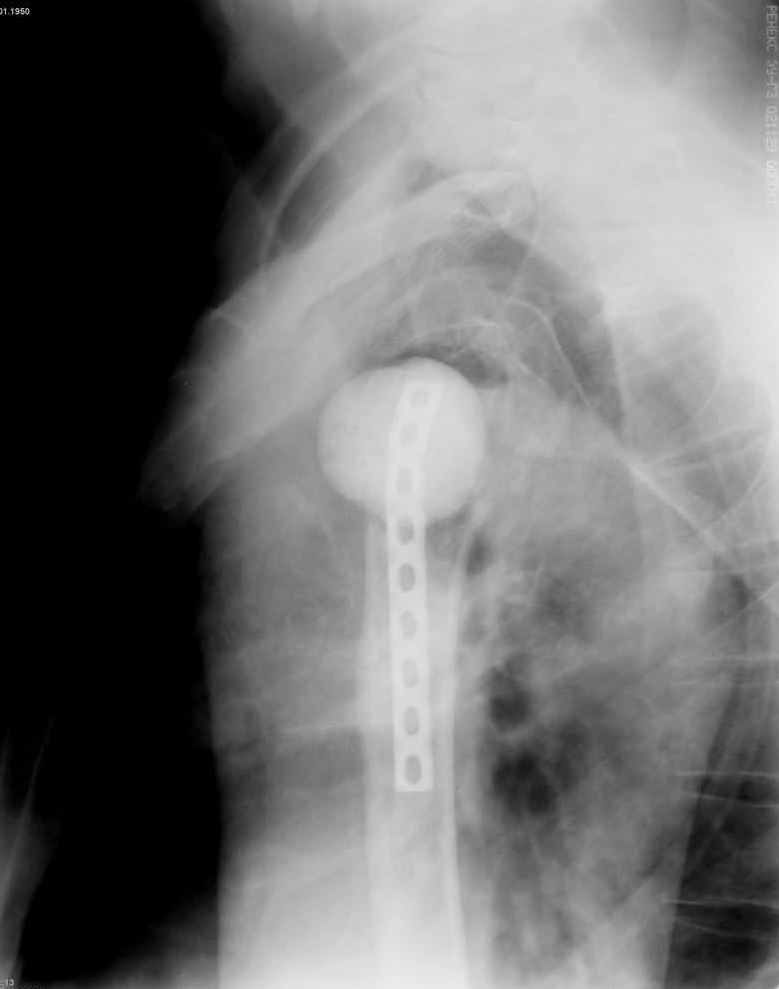

Уважаемые коллеги. Недавно из нашего отделения был выписан пациент 54 лет с закрытым переломом плечевой кости. Из анамнеза: за 2 дня до поступления в НИИСП, в состоянии алкогольного опьянения упал с лестницы на даче (высота 3-4 метра) с упором на правую руку. Через двое суток обратился за медицинской помощью. Доставлен бригадой "Скорой помощи".Правый плечевой сустав умеренно деформирован. По внутренней поверхности плеча имеется кровоподтек. При пальпации плечевого сустава имеется умеренная болезненность. Активные и пассивные движения болезненные. Снижена чувствительность по тыльной поверхности пальцев кисти и отсутствует активное разгибание кисти и пальцев. Имеется подкожная эмфизема шеи, верхней половины грудной клетки (рис 1, 2). На рентгенограмме: оскольчатый перелом головки плечевой кости со значительным смещением, перелом 2-3 ребер справа, тканевая эмфизема (рис 3). КТ при поступлении: перелом головки плечевой кости в области анатомической шейки со смещением отломка головки в грудную полость, правосторонний гидроторакс, перелом 2-3-4 ребер справа. (рис 4). Через двое суток после поступления выполнена операция: атипичная торакотомия, эвакуация свернувшегося гемоторакса, удаление инородного тела (головки плечевой кости) из плевральной полости (при этом выявлено имеющееся повреждение париетального и висцерального листков плевры) (рис. 5), дренирование плевральной полости, замещение проксимального конца плечевой кости спейсером из костного цемента с антибиотиком (рис. 6). Послеоперационный период протекал гладко. При контрольной рентгенографии положение спейсера удовлетворительное (рис. 7, 8). Дренаж из плевральной полости удален через 3 суток после вмешательства. Послеоперационная рана зажила первичным натяжением. Через 12 дней после операции больной выписан на амбулаторное лечение.

Через 3 месяца планируется повторная госпитализация для выполнения эндопротезирования правого плечевого сустава. Похожий, но менее тяжелый, случай был показан в 2004 году на сайте журнала J Bone Joint Surg Am. (http://www.jbjs.org/Image_Quiz/2004/may04/iqmay04_p1.shtml).

После операции мы не исключали развитие пневмоторакса, плеврита, гемоторакса или эмпиемы плевры. Поэтому мы посчитали возможным заместить дефект плечевой кости спейсером с антибиотиком, а эндопротезирование выполнить в «чистых» условиях.